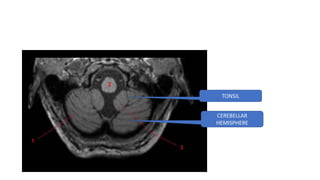

CEREBELLUM

TONSIL

CEREBELLAR

HEMISPHERE

VERMIS

MIDDLE CEREBELLAR PEDUNCLE

SUPERI0R CEREBELLAR PEDUNCLE -MIDBRAIN LEVEL

HORRIZONTAL FISSURE

SUPERIOR CEREBELLAR PEDUNCLE -MIDBRAIN LEVEL

MIDDLE CEREBELLAR PEDUNCLE AT PONS